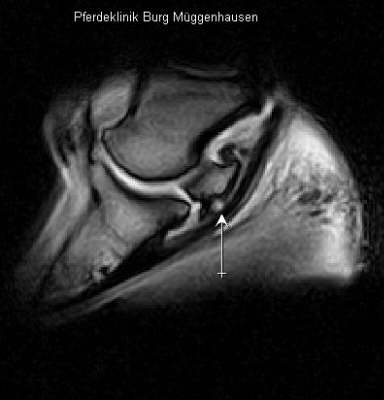

Deutliche weiße Zone im Strahlbein. Im MRT stellt sich Flüssigkeit weiß dar, womit der Nachweis des Einbruchs der Gleitfläche erbracht ist.